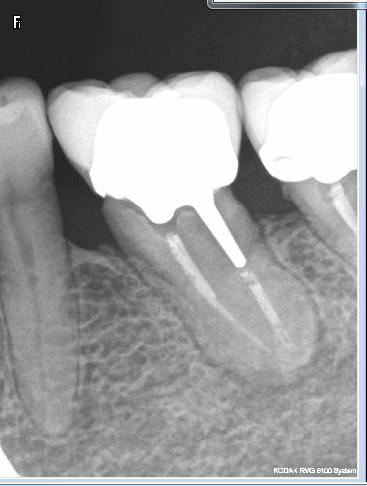

OK. Conventionnés ? Une tante est allée voir un exclusif pour RTE sur cette 36. 900 euros le RTE.

C'est con j'ai pas eu la présence d'esprit de lui faire une radio pour voir la différence quand elle est passée dans le coin la semaine dernière ( elle habite Paris). Meme elle qui a pourtant de la caillasse a trouvé ca un peu cher. Moi aussi d'ailleurs on se rapproche du cout d'un tt implantaire avec beaucoup moins de chances de réussite-))))